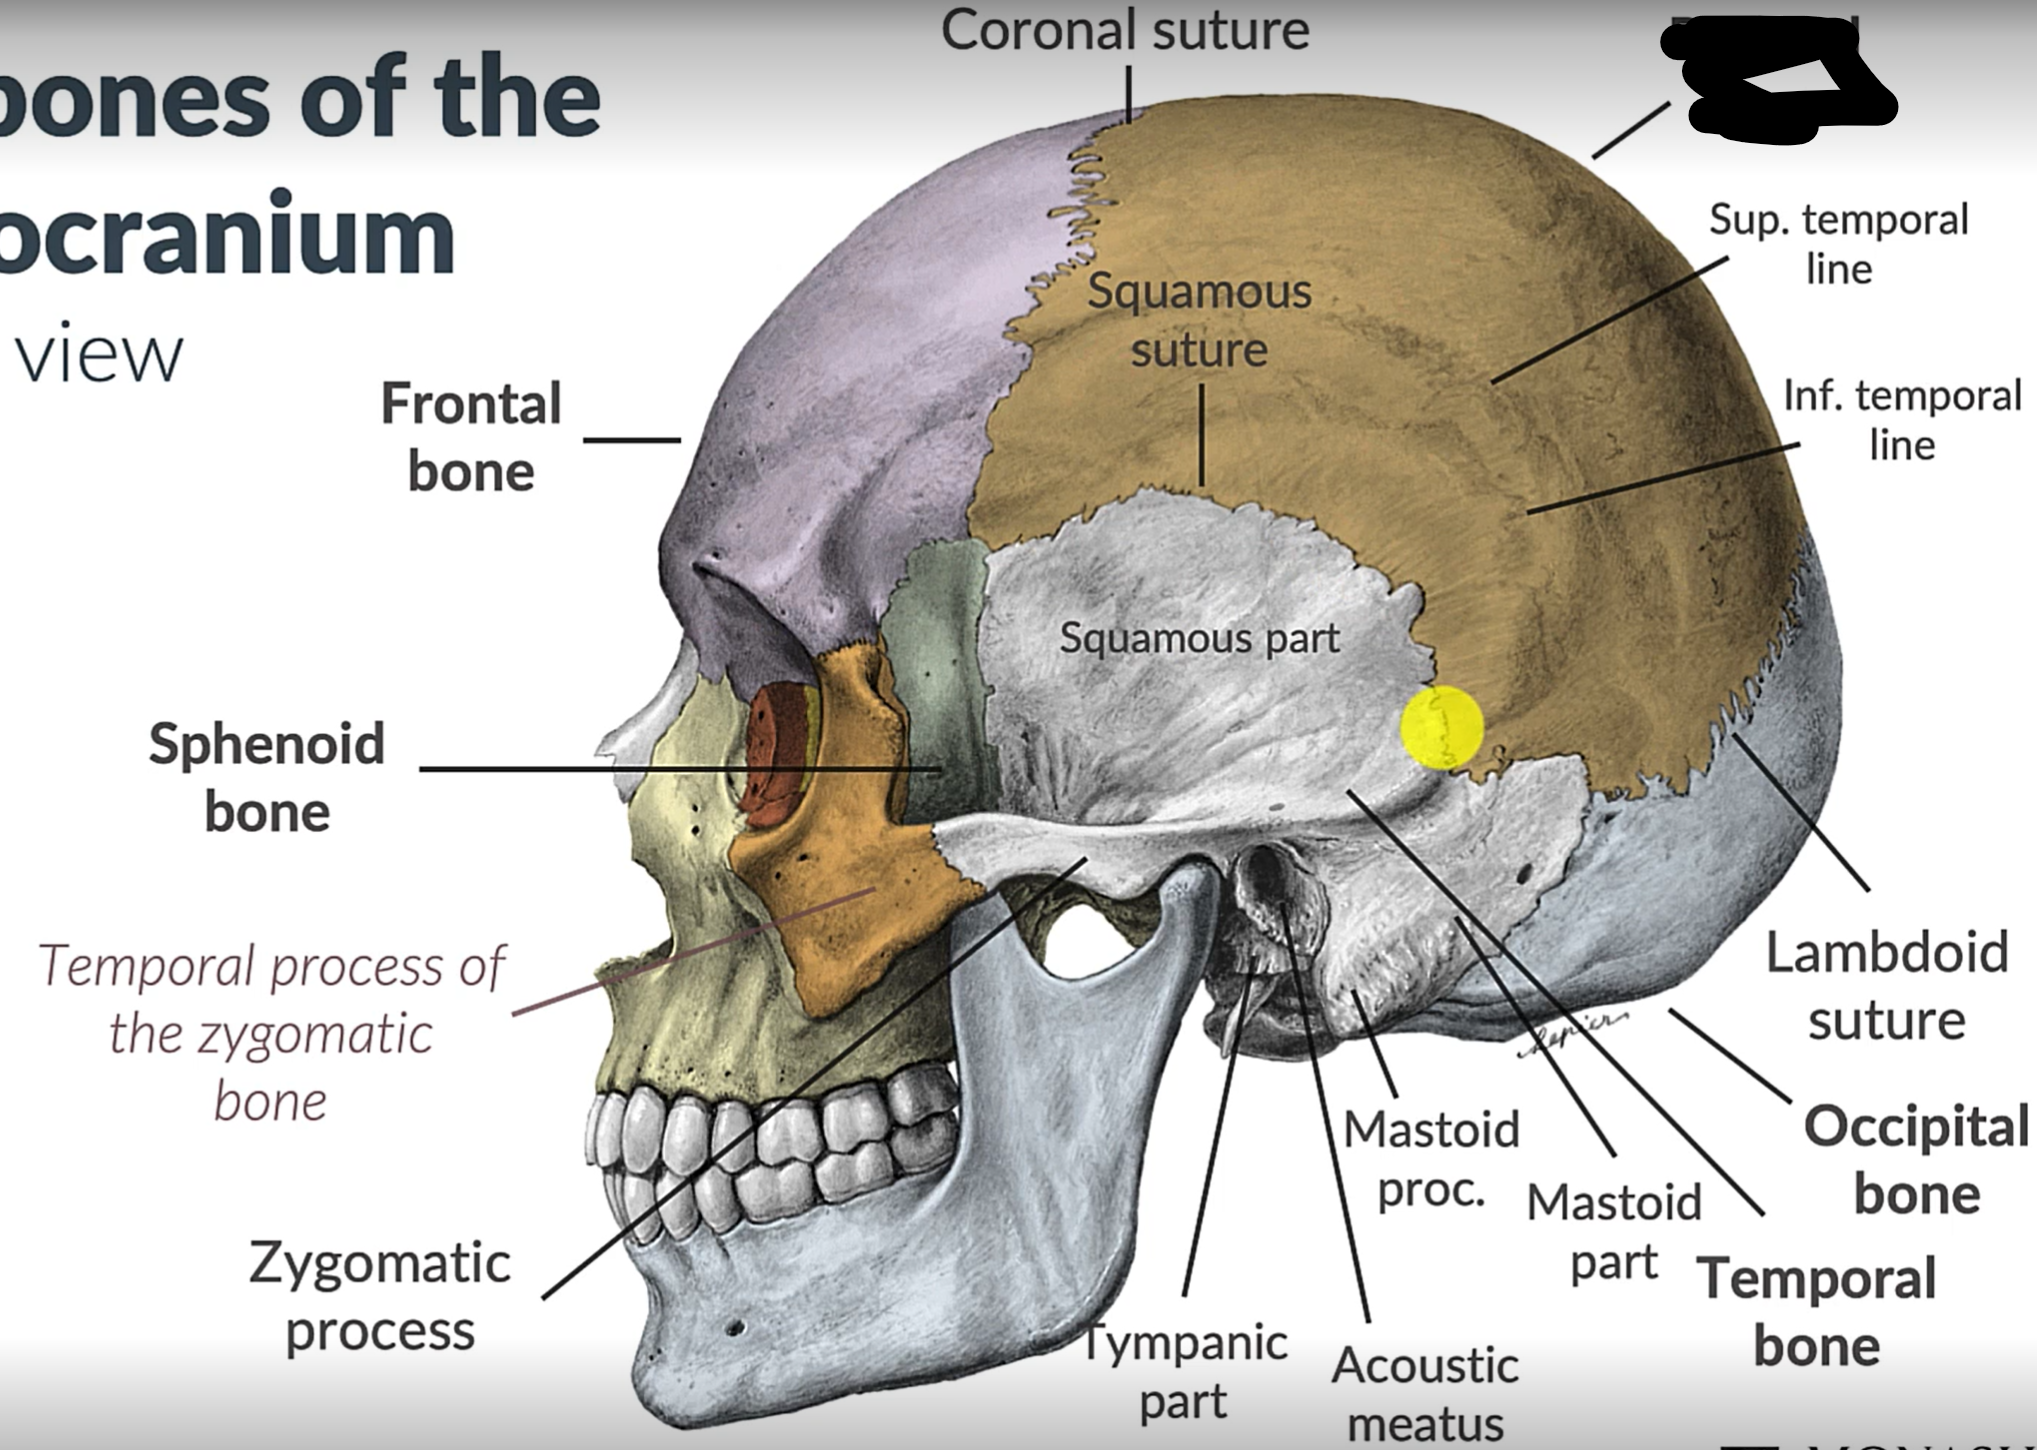

What bones make up the neurocranium?

Occipital bone (1)

Parietal bones (2)

Frontal bone (1)

Temporal bones (2)

Sphenoid (1)

Ethmoid (1)

What are the 4 cranial sutures and what do they separate?

Lambdoid - separates occipital from parietal and temporal

Sagittal - extends between parietal bones

Coronal - divides frontal and parietal bones

Squamous - either side of cranium, separates temporal and parietal bones

Parietal bone

Frontal bone

Temporal bone

Sphenoid bone

Zygomatic bone

Coronal suture

Squamous suture

Lambdoid suture

Occipital bone

Temporal bone

Zygomatic process

Sphenoid bone